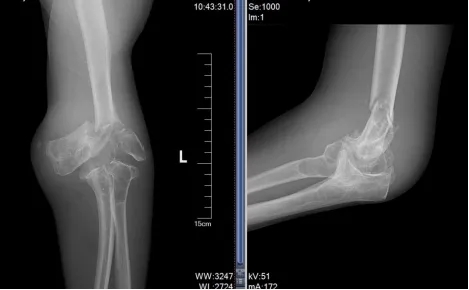

术前X线

面对这一复杂的病例,贾丙申主任带领科室团队进行了周密的术前规划,精确掌握郭先生肘关节的畸形程度和骨骼形态。经过多次深入的术前讨论,最终制定了个性化的手术方案,精准预判了术中可能遇到的骨骼缺损、软组织平衡及神经血管保护等一系列难题。